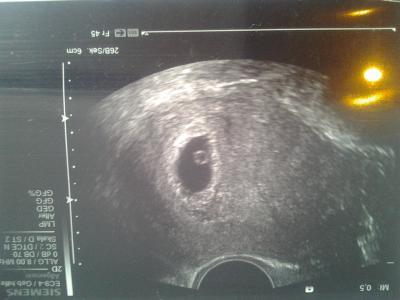

Ich bin jetzt schon 4 mal im kh gewesen... jedes mal darf ich mir anhören i h mache zu viel Panik... hallllllo bei hellen Blutungen.... und ich nicht weiss woher die kommen... die haben leicht reden.... Die Blutung gestern war vom gebärmutterhals da ist irgendwas gerötet was nun blutet .. klasse und dann noch die untrstellung ich hätte Sex gehabt... mein freund hat mich komisch angeschaut weil wir ja auf Sex wegen dem ganzen verzichten..... Ich hoffe nun sehr das es mit den kh,s nun aufhört....

Bild zu gestern schon wieder KH ich mag nicht mehr...+ foto - Forum für August - Mamis